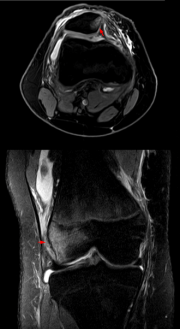

(Abb. 3) - MRT nach Patellaluxation. An der medialen Seite der Patella (oberes Bild) und der korrespondierenden Seite des lateralen Femurkondylus (unten), an der die Patella angeschlagen ist, finden sich Zeichen der Knochenkontusion.